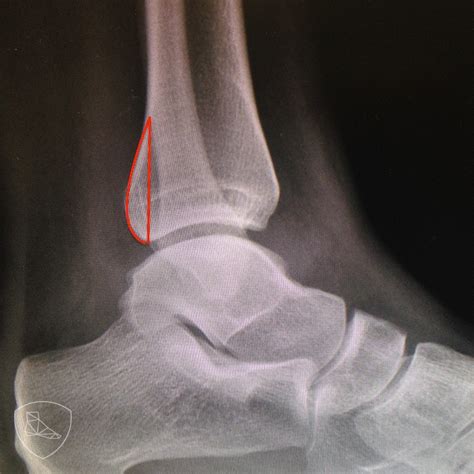

Fractura Maleolo Peroneo Sin Desplazamiento, MALÉOLO PERONEO | Qué es, significado, ubicación, función y lesiones, 4.03 MB, 02:56, 12,945, FisioOnline, 2020-12-15T19:13:43.000000Z, 3, Do You Need an Ankle X-Ray? - Therapydia Portland, therapydiaportland.com, 2000 x 905, jpeg, WebLa fractura del tobillo es una lesión relativamente frecuente. Se caracteriza por la ruptura de la prominencia ósea en la parte externa (tercio distal del. WebFractura no desplazada maléolo peroneo D Mi hija el día 03-03-12 se fracturo el maléolo peroneo sin desplazamiento y el han puesto una férula suropédica. Le estamos., 20, fractura-maleolo-peroneo-sin-desplazamiento, Novedades y Muebles WebLa fractura del tobillo es una lesión relativamente frecuente. Se caracteriza por la ruptura de la prominencia ósea en la parte externa (tercio distal del. WebFractura no desplazada maléolo peroneo D Mi hija el día 03-03-12 se fracturo el maléolo peroneo sin desplazamiento y el han puesto una férula suropédica. Le estamos.

WebAnatomía interactiva. El tobillo está conformado por diferentes zonas anatómicas esenciales para que podamos caminar y desplazarnos. Existen dos zonas prominentes en el tobillo. WebLa fractura puede desplazarse, si es el caso, debe corregirse quirúrgicamente. Pseudoartrosis, esto significa que aún no existe una conexión ósea estable entre los. WebLas fracturas de tobillo se producen en el maléolo medial o posterior de la tibia y/o el maléolo lateral del peroné. Estas fracturas pueden ser estables o inestables.. WebUna fractura se puede clasificar según la ubicación de los fragmentos óseos en: Compuesto: tras la fractura, los fragmentos óseos no sufren desplazamientos con. WebEn esas fracturas se recomienda no cargar la pierna 4-6 semanas. Aunque el mayor riesgo de desplazamiento se produce en las 3 primeras semanas, es posible que se haya. WebEl tiempo de recuperación de una fractura de maleolo peroneal sin desplazamiento suele ser de entre 6 a 12 semanas. ¿Cuánto tarda en curar una fractura de maleolo externo? A. WebFractura del maléolo externo del peroné sin desplazamiento apoyar pie. El 15/11/2013 hace hoy 16 días me fracturé el maléolo externo del peroné sin deplazamiento. Me.